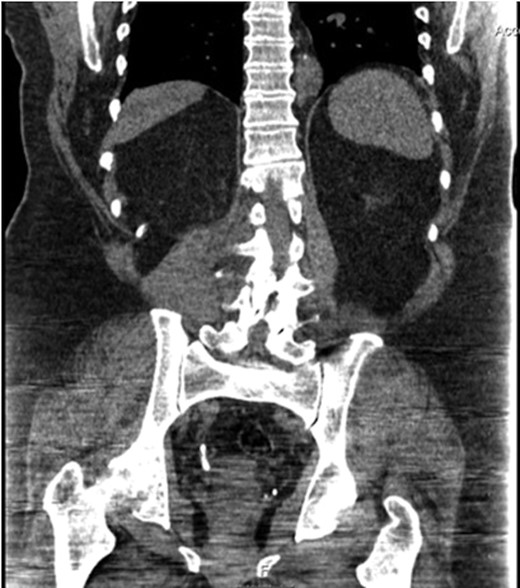

A 63-year-old man presented with a 4-day history of right sided loin to groin pain. Non-contrast CT of the urinary tract (KUB) revealed multiple right distal ureteric calculi measuring 7 mm by 22 mm with mild dilatation of the right pelvicalyceal system (Fig. 1). There were multiple bilateral renal calculi, the largest measuring 7 mm. Urine culture revealed mixed growth. His renal function was not altered from baseline and electrolytes were unremarkable.

CT scan demonstrating contiguous right distal ureteric calculi measuring 7 mm by 22 mm.